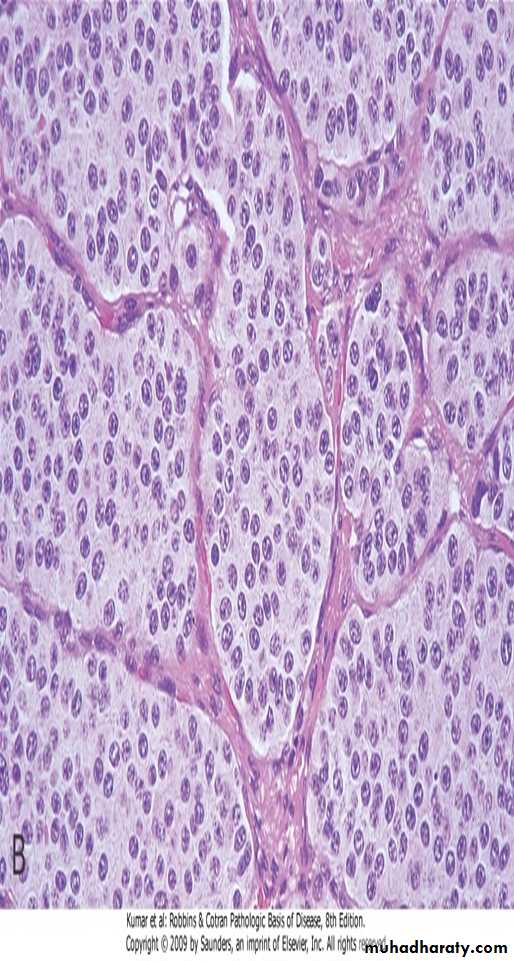

Several coalescent collagenous silicotic nodules